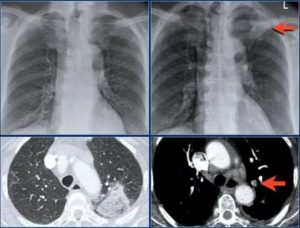

Как выглядят легкие коронавирусных больных на КТ

Еще во время январской вспышки эпидемии в Китае врачи быстро выяснили, что COVID-19 поражает легкие. Это проявилось на рентгенограммах и КТ.

При рентгеновском излучении наиболее плотные ткани, такие как кости, поглощают лучи и поэтому выглядят белыми. Наименее плотные, как легкие, состоящие в основном из воздуха, – черными. Серыми выглядят ткани, которые частично задерживают излучение.

- Синдром «матового стекла»

Вот один из вариантов того, как зоны легочной патологии выглядят на КТ коронавирусной пациентки: бледные помутнения, которые в радиологии называют «синдромом матового стекла».

«Матовое стекло» показывает, что легочная ткань, которая должна быть воздушной и не задерживать лучи, в этих зонах незначительно уплотнилась. Значит, альвеолы – воздушные пузырьки, насыщающие кровь кислородом, частично заполнились патологическим жидкостным содержимым: это может быть воспалительная, отечная жидкость, кровь, гной, отмершие клетки и т.д.

- «Консолидация» легочной ткани

Если легочная ткань полностью потеряла воздушность, то она становится еще более плотной и непроглядной, чем «матовое стекло». Такой рисунок называют «консолидацией».

- Синдром «булыжной мостовой» / «Лоскутное одеяло»

Наконец, когда помутнения по типу «матового стекла» сочетаются с уплотнением перегородок из соединительной ткани вокруг легочных долек, то внешне это напоминает разнообразные куски брусчатки в мостовой или лоскутное одеяло – отсюда и название патологической картины в легких.

Ниже показаны части томограммы у февральских пациентов с коронавирусом:

a – «матовое стекло»

b – «булыжная мостовая»

c – «консолидация»